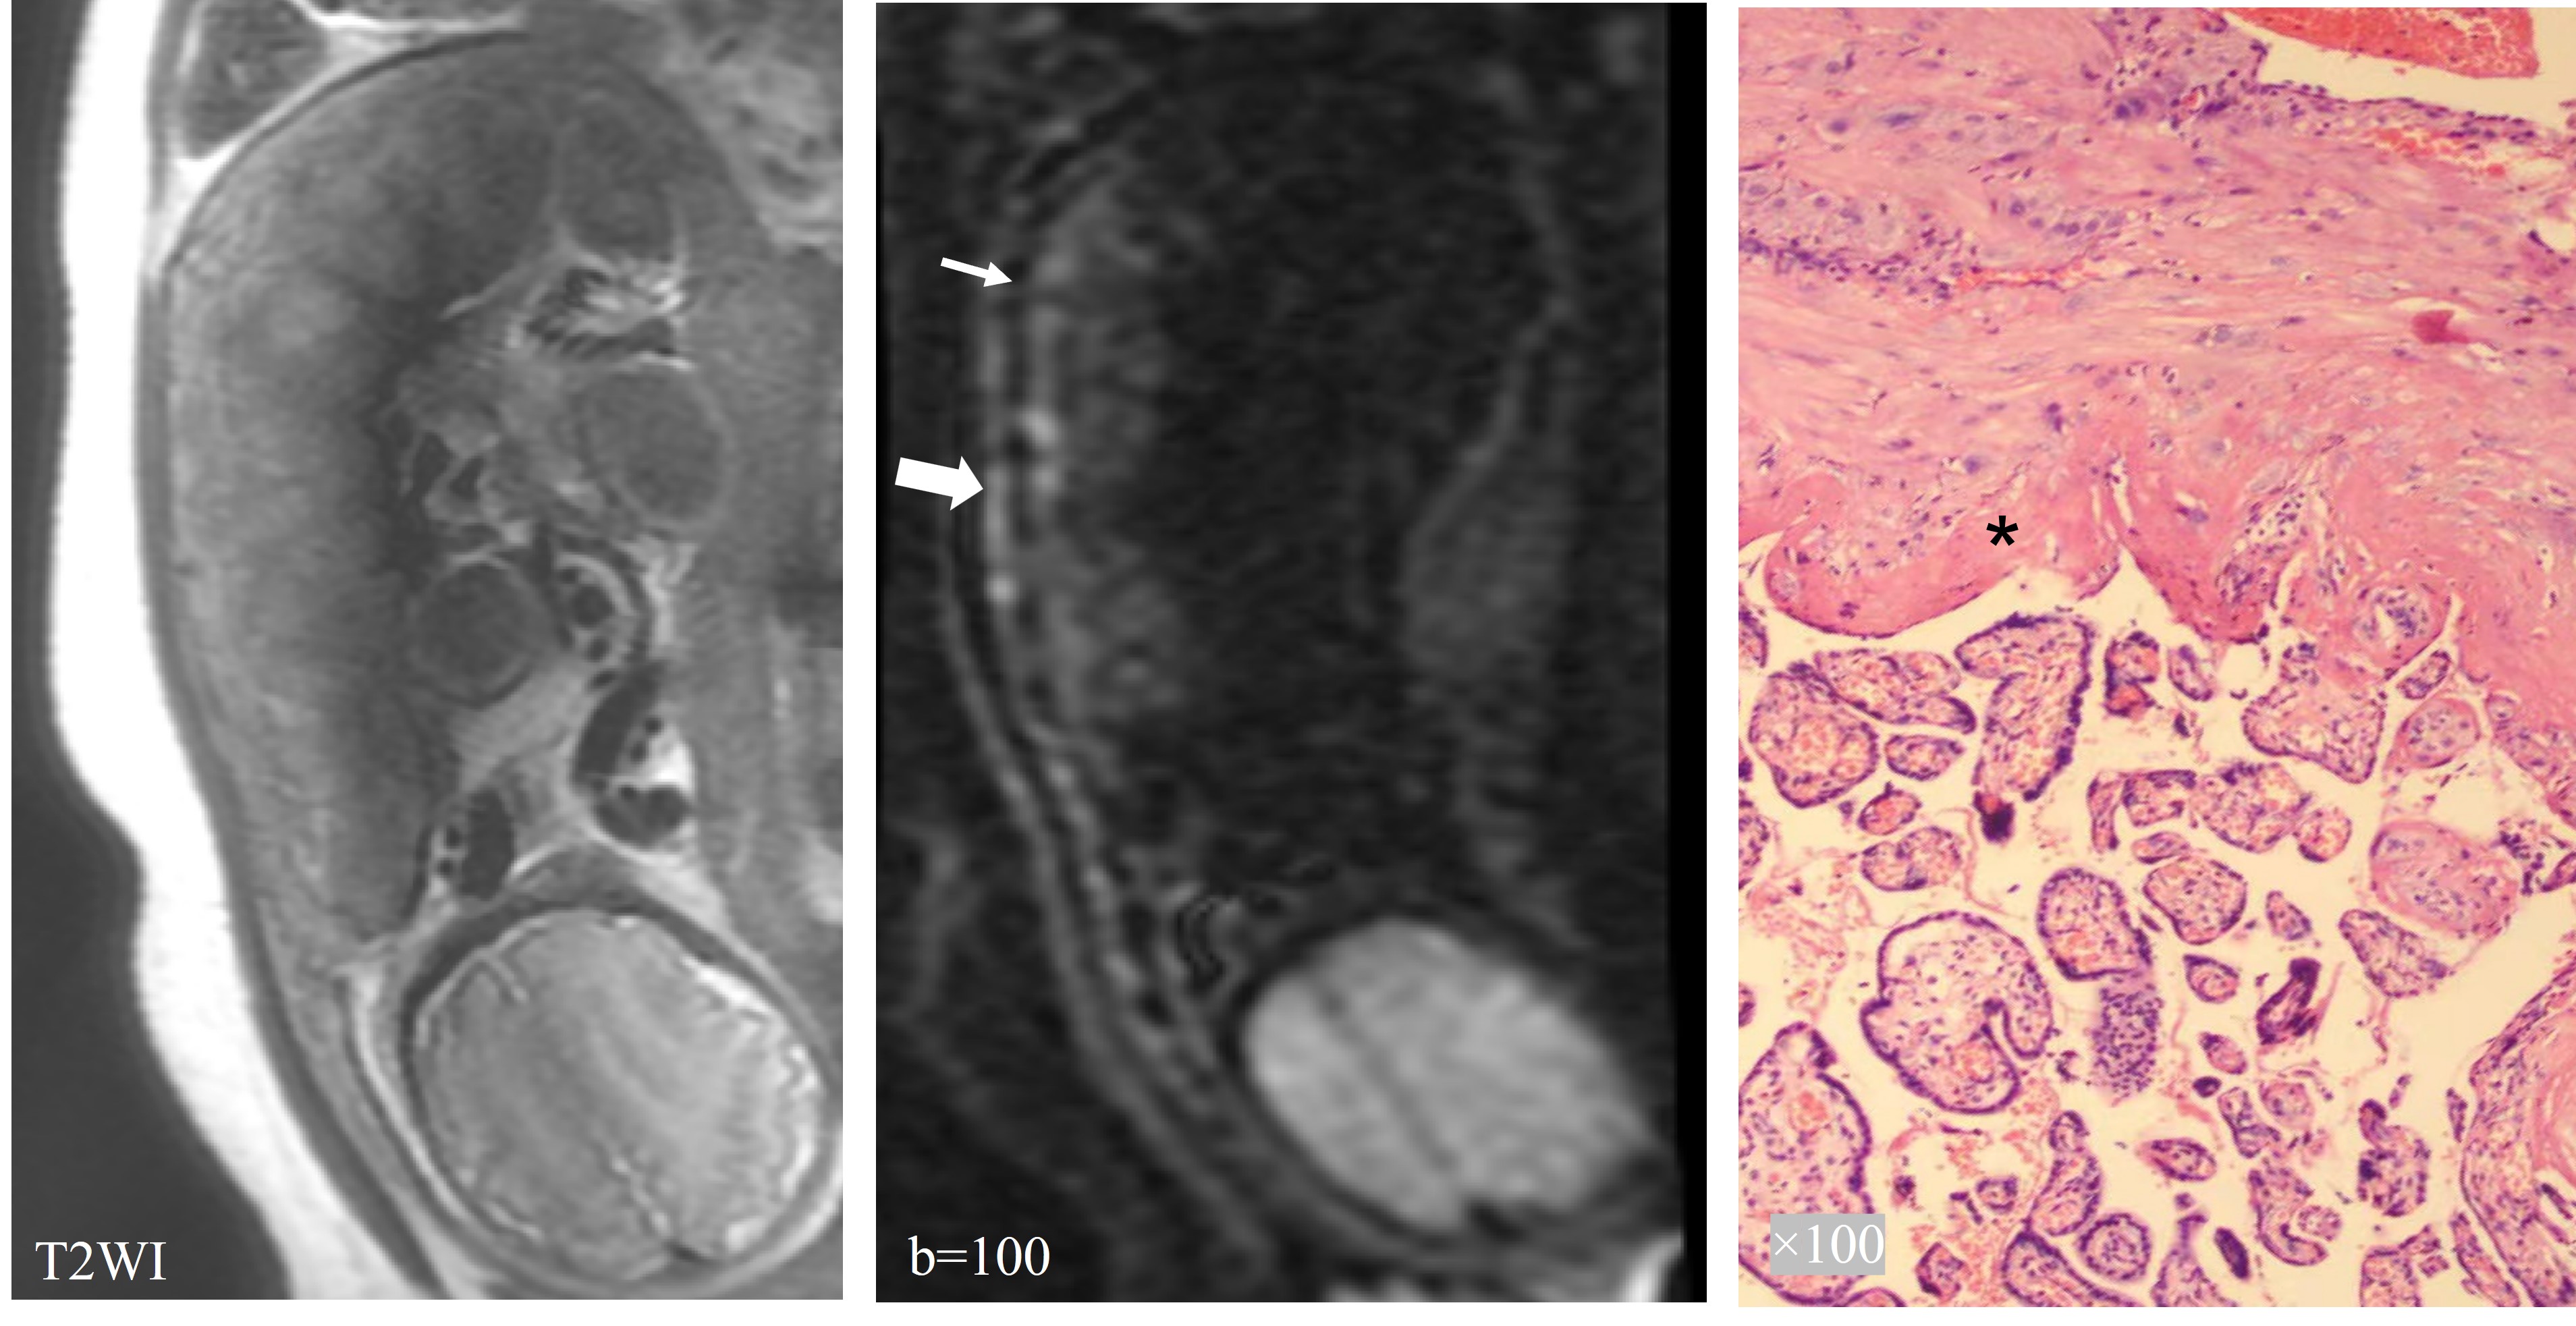

Figure 4 showed the characteristics of IVIM images of the placenta in patients with PA. Part of the basal plate disappeared (>10mm), and the myometrium could not be separated from placenta. T2WI images displayed partial bulge of placenta with PI, and IVIM images showed interrupted low signal bands of the basal layer at the same location (Figure 5). T2-dark bands, discontinuous myometrium, abnormal intraplacental vascularity and placental bulge are some of the most common signs of PAS diagnosed by conventional MRI. As shown in Table 2, comparing these signs of conventional MRI, sign of discontinuous basal plate in IVIM achieved the highest diagnostic sensitivity (92.6%) with an AUC of 0.892.

Figure 4. The characteristics of IVIM images of the placenta in patients with PA.Part of the basal plate disappeared (>10mm), and the myometrium could not be separated from placenta.

Figure 4. The characteristics of IVIM images of the placenta in patients with PI. IVIM images showed interrupted low signal bands of the basal layer at the same location.